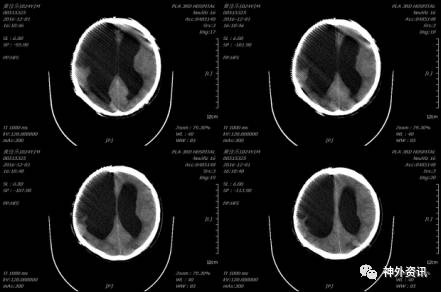

2016-10-11血常规:细胞25.42×109/L、降钙素原测定(PCT)0.40ng/ml,2016-10-10发现分流管处头皮水肿,行B超示:皮下组织水肿,头颅CT示较前无明显变化。腰穿检查示:无色浑浊、白细胞手工计数1958.00×106/L、中性粒细胞0.89、淋巴细胞0.11、葡萄糖(GLU)1.46mmol/L、脑脊液蛋白(PRO)0.97g/L,压颈不通畅。考虑颅内感染,再次建议家属行分流管取出术,2016-10-14行分流管取出术,术后行导管细菌培养及图片未发现细菌,2016-10-17脑脊液细菌图片:偶见革兰氏阴性杆菌,但培养未发现细菌,继续给予万古霉素、美罗培兰抗感染至3次脑脊液基本正常后于2016-11-12停药,患者逐渐恢复,意识清楚,言语清晰。

2016-10-15复查头颅CT示:拔出引流管后未见脑室继续扩大。

胸部情况较前明显好转,于2016-12-01再次复查头颅CT示未见脑室进一步扩大。

后患者逐渐康复,未再行脑室腹腔分流术,耐受良好,于2017年3月复查头颅CT未见脑室明显扩大,意识清楚,言语清晰,对答切题,扶物下可自主行走,生活大部分基本自理。

2017-03-30头颅CT示: